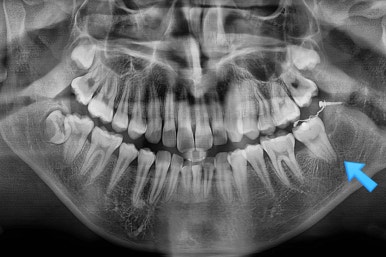

X-ray를 보면 사랑니가 어부바 하고 있어서 나와야 될 어금니가 짓눌려 있는 양상이었어요.

이 경우 방향을 잘못잡아서 바로 앞 어금니도 밀어버리거나 해를 가할 수 있는 상황이었어요.

사랑니가 잘못나는 바람에 사랑니 포함 치아 3개가 문제가 될 수 있는 상황이었어요.